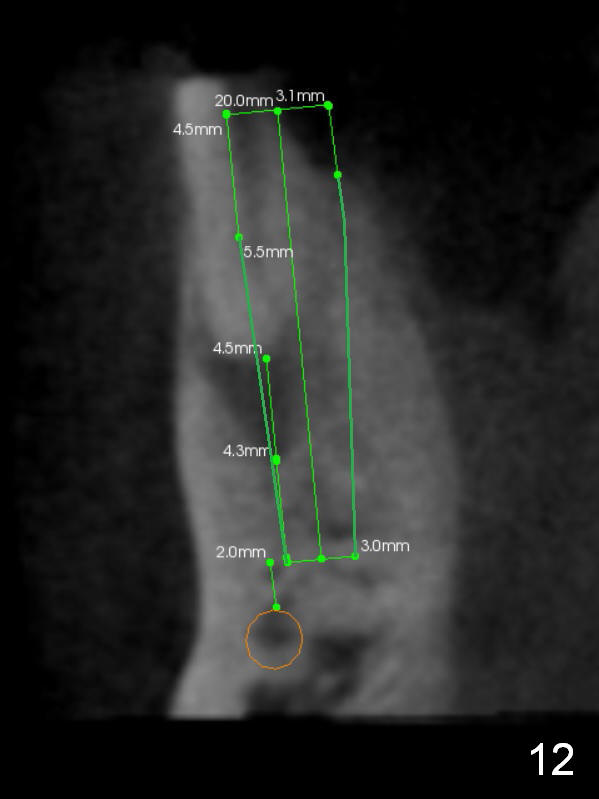

CT sagittal section shows that it is possible to place 4.5x20 mm implant (Fig.6). Axial (Fig.7) and coronal (Fig.9) sections show that the lingual (L) plate is much thicker than the buccal (B) one. To prevent the implant being buccally deviated, a Lindermann bur is used after extraction (black area in Fig.8,10) to remove ~ 1mm bone from the lingual plate (red area in Fig.8,11). A 2 mm pilot drill is placed as lingual as possible (green in Fig.8,11). If the implant (Fig.12) starts to deviate buccally while being placed, remove it from the osteotomy and remove more bone from the lingual plate. Place the implant again and monitor the trajectory tightly.